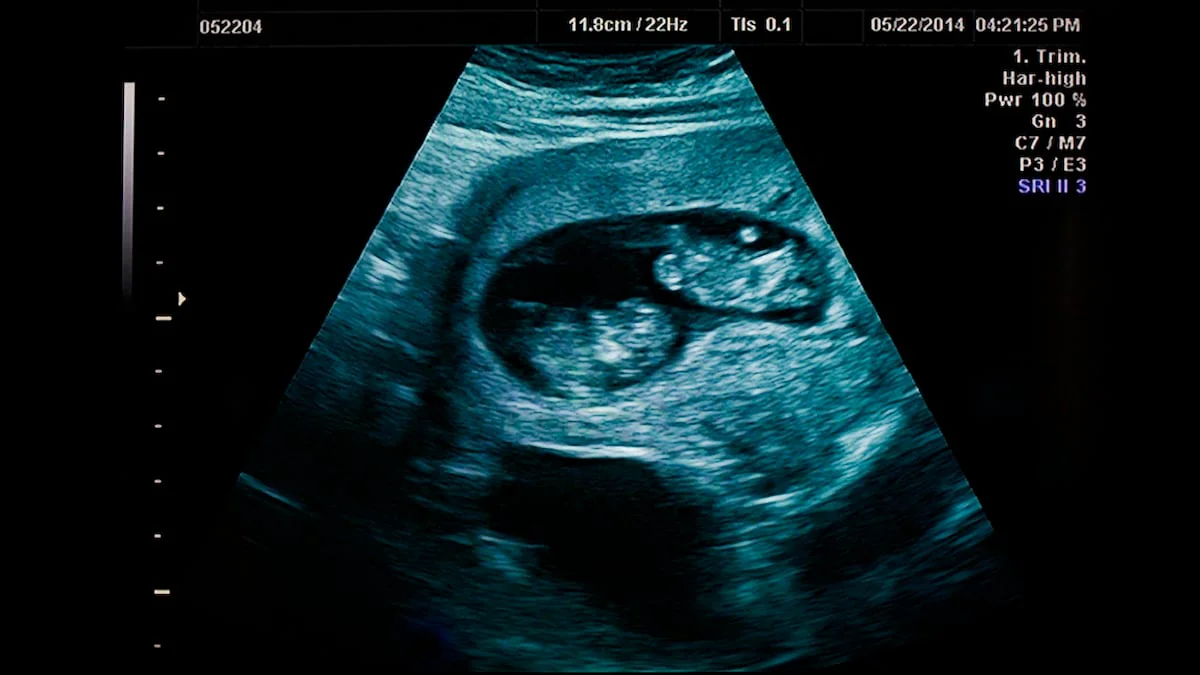

Eine dieser freiwilligen Leihmütter ist Courtney Williams, die aktuell auch als solche schwanger ist. Allerdings stellte sich heraus, dass sie nicht mit einem Baby schwanger ist, sondern mit Zwillingen. Während es regelmäßig vorkommt, dass entgegen der Erwartungen zwei Kinder unterwegs sind, sind die anderen Details des Falls alles andere als gewöhnlich. Denn wie Untersuchungen ergaben, sind die beiden Zwillinge überhaupt keine Geschwister.

Eines der Babys entstand aus der befruchteten Eizelle, die Courtney Williams eingesetzt wurde und ist folglich das Kind der sogenannten Wunscheltern. Das andere jedoch ist von Courtney und ihrem Mann; es muss kurz nach der künstlichen Befruchtung gezeugt worden sein. Rein rechtlich ist die Lage damit klar, zumal man mit Tests schnell herausfinden kann, welcher Zwilling zu welchen Eltern gehört. Medizinisch ist der Fall allerdings außergewöhnlich.